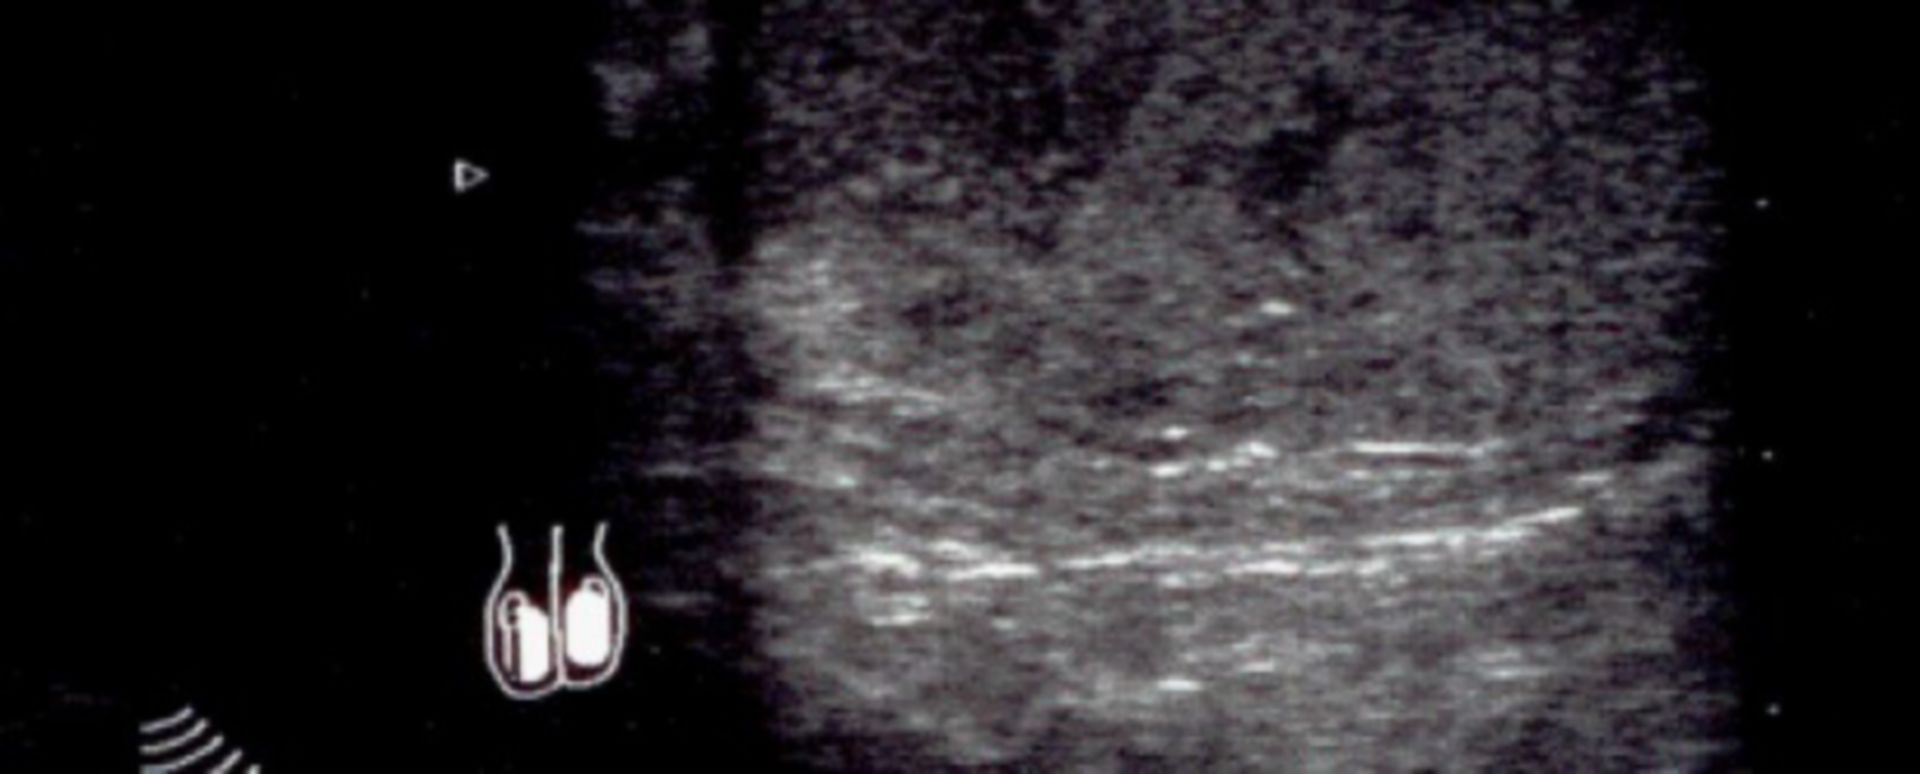

Wie lange hat man nach der Vasektomie geschwollene Hoden? Nach einer Vasektomie können leichte und ziehende Schmerzen im Hodensack für etwa 2-3 Tage auftreten. Risiken und Nebenwirkungen einer Vasektomie: Entzündungen von Hoden und Nebenhoden, erneute Zeugungsfähigkeit, Narbenwucherung, Schmerzen; insbesondere im Hoden- und Leistenbereich. Dieser ist am geschwollenen Kopf zwar nicht druckempfindlich, dafür aber nach wie vor am unteren Ende des Schwanzes

Vasektomie UroGynZentrum Wall Wuppertal. Dieser sogenannte 'Post-Vasektomie-Schmerz' (auch post vasectomy pain syndrome) kann kurz nach der Vasektomie, manchmal aber auch erst mit längerer Verzögerung beginnen Weiterhin merke ich dass sich der Nebenhoden auf der Rückseite des Hodens im Bereich des.